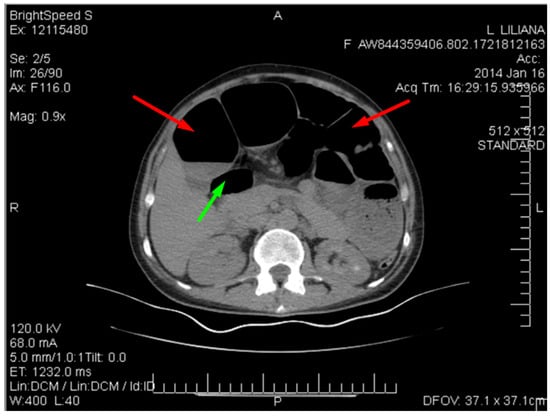

Figure 3 shows the contrast-enhanced CT scan of the abdomen and pelvis being performed, which provided a detailed view of the abdominal cavity.

Figure 5 shows the spiralling appearance of the mesenteric vessels.

The CT scan revealed distention of the small intestine and detected an ileal loop that appeared looped around a blood vessel, validating the diagnosis of an intestinal volvulus.

Figure 3. CT image of the intestinal volvulus—“whirlpool sign” (red arrow), air loops (green arrow).